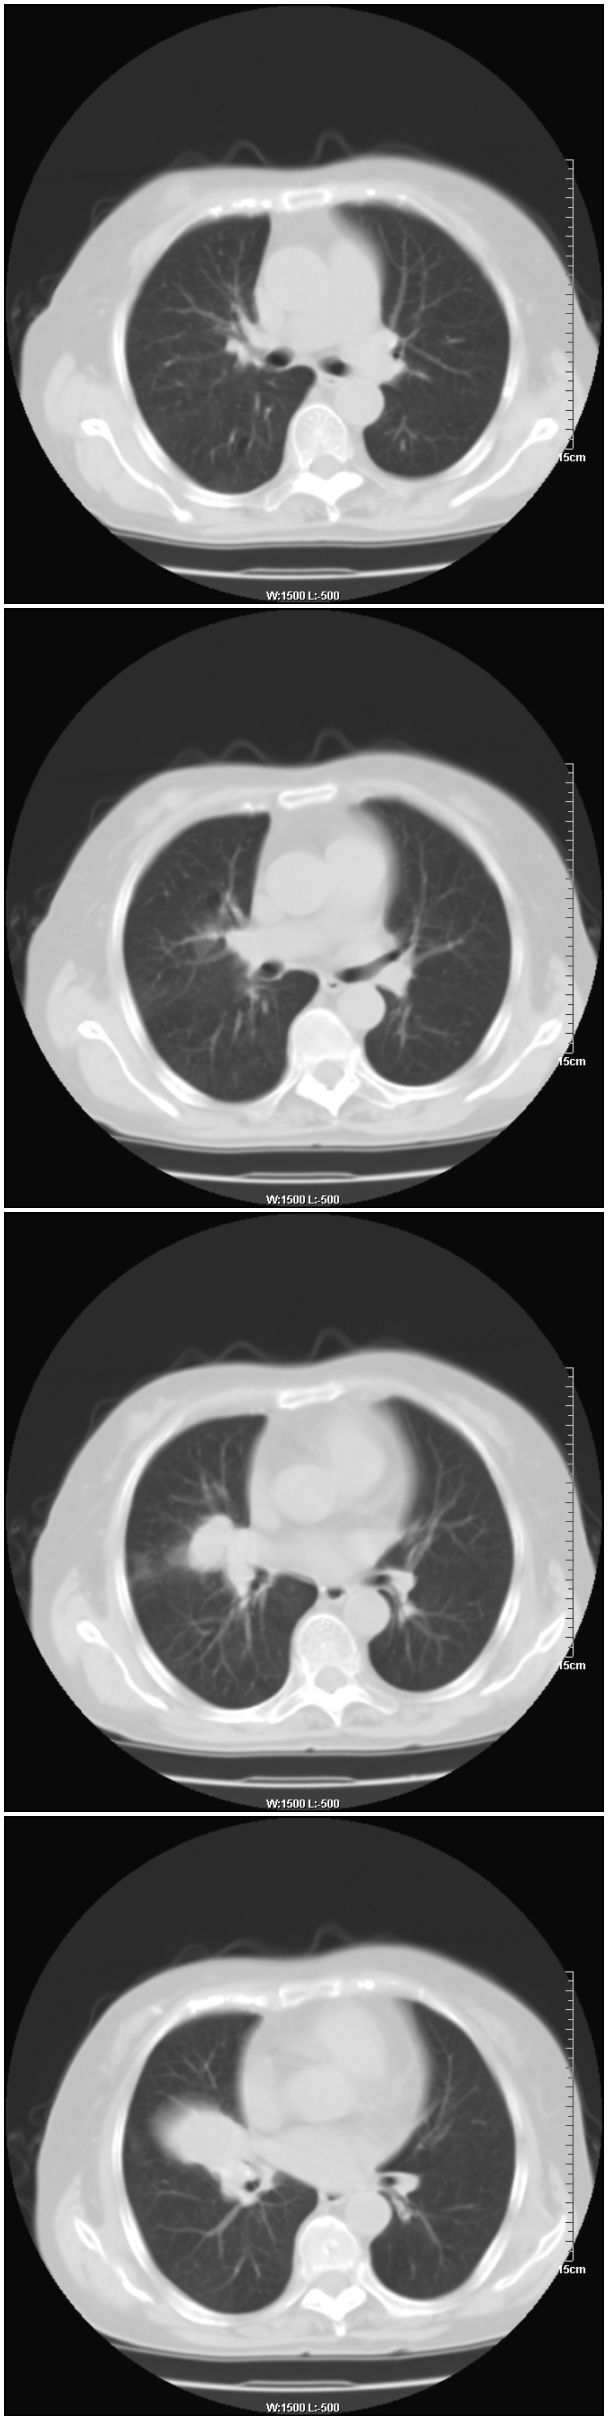

女性,78岁。术前体检发现肺部病变,看看还有什么问题?肺病变是什么性质?

在右侧,支持!右肺中心型肺癌! 右乳腺肿物。

支持!右肺中叶中心型肺癌!右侧乳腺内上象限结节,建议薄扫

右侧乳腺占位,右肺门结节状-----肿大淋巴结?

乳腺病变在右侧   是否可考虑为乳腺癌肺部转移

应该是右肺中心型肺癌,乳腺的肿物应该在右侧,看见右侧有结节,并乳头凹陷

1.右侧乳腺病变。

2.右肺病变,考虑:肺癌可能性大。(病变边缘光滑,硬化性血管瘤或其他良性肿瘤待除外)

右侧乳腺内上象限结节影,边缘模糊,右肺病变相邻支气管内见软组织密度影及斑点样钙化灶,考虑肺癌可能性大,建议结合纤支镜检查。

右肺中央型肺癌伴中叶肺不张。

右乳腺内结节病灶,如增强扫描动脉期结节呈明显强化可考虑乳癌。